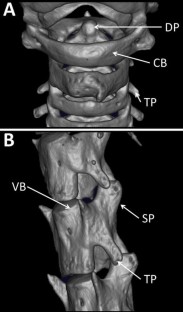

Fig. 1

DP:

Dens process

CB:

Cervical bone

TP:

Transverse process

SP:

Spinous process

VB:

Vertebral body